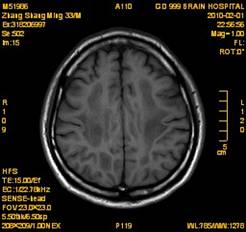

案例1 患者,男,33岁, 海洛因脑病的头颅MR。表现为双侧大脑后部皮层下白质、双侧内囊后肢、枕叶白质、胼胝体压部、中脑、桥脑、双侧小脑半球齿状核质及双侧桥臂多发对称性片状及斑片状长T1长T2异常信号影,FLAIR序列呈高信号,其中双侧内囊后肢表现为特异的“八字征”,双侧小脑半球齿状

核质表现为对称的“蝶翼征”,脑干病变呈“蟹钳征”及“中空征”。增强后双侧半卵圆中心、双侧枕叶白质及双侧小脑半球病变内或边缘中度强化影。给予患者抗炎、脱水、疏通血管及营养神经等药物治疗,一个月后痊愈出院。